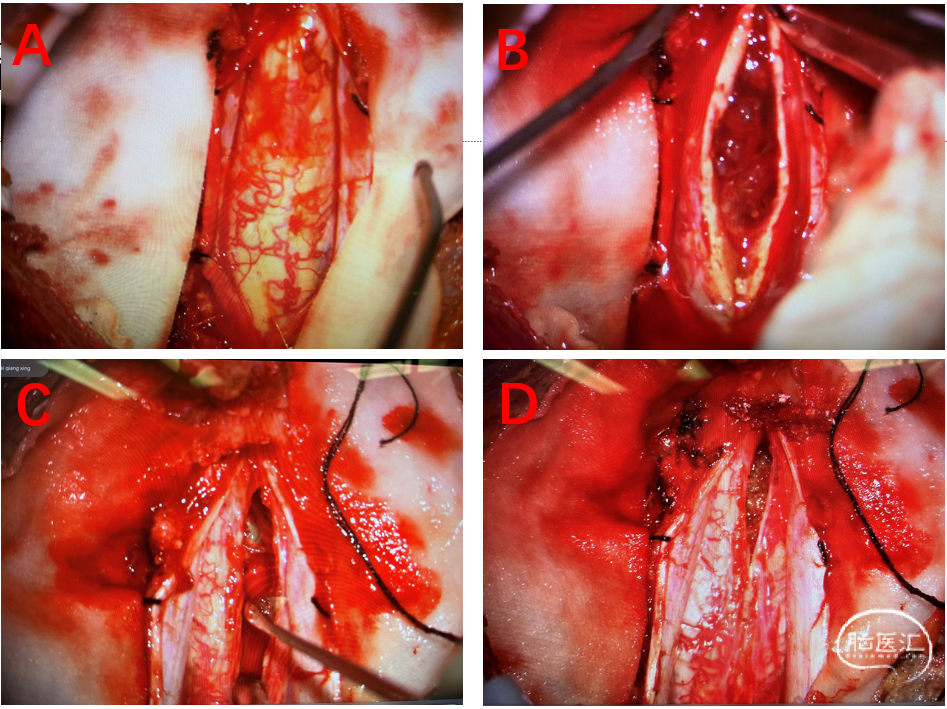

置入显微镜,显微镜剪开硬脊膜,悬吊硬脊膜于两侧肌肉,见脊髓组织肿胀,部分有黄染(图2A)。双极电刀小电流电凝脊髓后正中皮质后,使用尖刀严格沿着后正中沟切开脊髓组织5mm,剥离子轻柔纵行分开脊髓(图2C),见髓内有囊实混合性占位病变,大小约5.6cmx1.2cmx1.6cm,病灶两端脊髓明显扩张、囊变,脊髓受肿瘤压迫推挤明显变薄。病变呈灰褐色,质地稍韧,血供丰富(图2B),在术中电生理监测下细轻柔分离肿瘤与周围的脊髓。超声吸引系统配合显微剪先从瘤腔分块切除大部分肿瘤。接着小心剥离残留肿瘤,最后切除镜下可见肿瘤(图2D)。

图2 手术过程